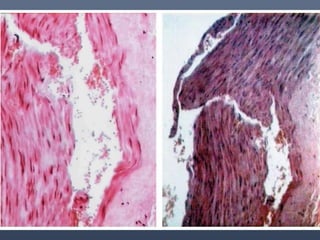

Vasculares:

•Desgarro trasversal de la túnica intima (signo de

Amussat).

•Desgarro de la adventicia (Signo de Etienne lesser).

•Desgarro en las venas yugulares el desgarro de la

túnica (signo de Ziemke).

Signos internos

Consisten en hemorragias de músculos del cuello y fracturas del hueso

hioides y de cartílagos de la laringe.

Pese a su similitud con la ahorcadura, en la estrangulación por medio de lazo

o cuerda son raras las lesiones vasculares.

SIGNOS INTERNOS Cuello: Traumatismosvasculares, musculares, óseos, laríngeos, neurológicos y digestivos. Vasculares: •Desgarro trasversal de la túnica intima (signo de Amussat). •Desgarro de la adventicia (Signo de Etienne lesser). •Desgarro en las venas yugulares el desgarro de la túnica (signo de Ziemke).

Signos internos Consisten enhemorragias de músculos del cuello y fracturas del hueso hioides y de cartílagos de la laringe. Pese a su similitud con la ahorcadura, en la estrangulación por medio de lazo o cuerda son raras las lesiones vasculares.